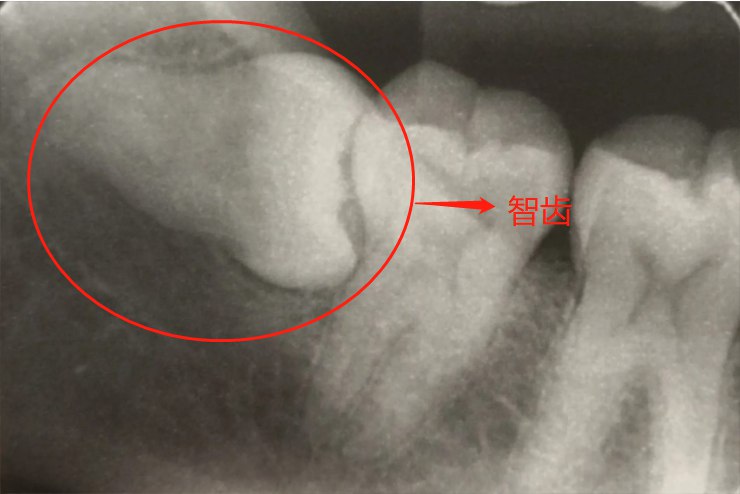

智齿是否长歪可通过拍摄口腔的曲面断层片判断,若智齿与相邻的牙齿高低不平,多代表智齿长歪了。